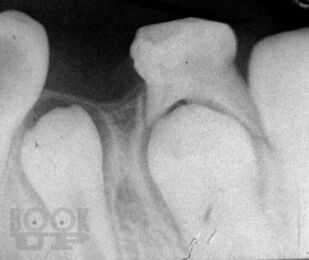

Учебное пособие составлено в соответствии с учебным планом по терапевтической стоматологии детского возраста. В нем описаны методики обследования зубочелюстной системы в детском возрасте, освещены особенности течения у детей патологических процессов в зубах, тканях пародонта и слизистой оболочке полости рта, проявления инфекционных заболеваний в челюстно-лицевой области. Детализировано своеобразие лечебной тактики при основных стоматологических заболеваниях, исходя из анатомо-физиологических особенностей детского организма. Отражены пути организации диспансеризации детского населения у стоматолога и плановой санации полости рта у детей.